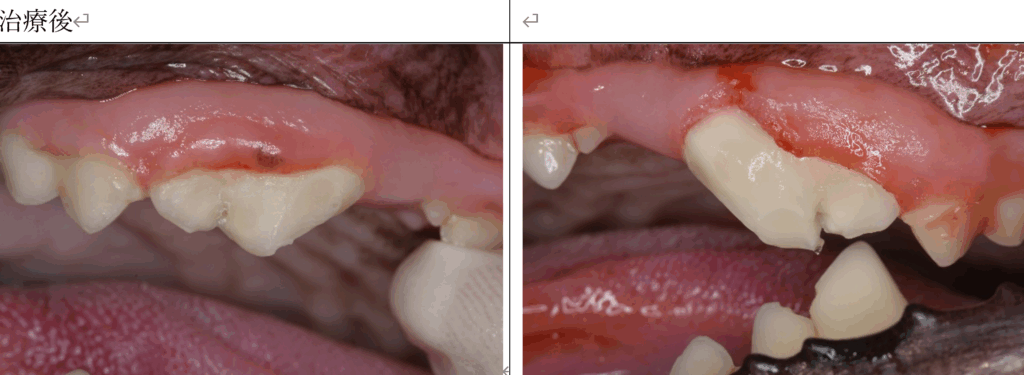

両側の露髄を伴う歯の破折の症例の紹介です。

右が露髄を伴う歯冠破折、左が露髄を伴う歯冠歯根破折です。

どちらも時間が経っているので、保存修復するには抜髄根管充填が必要です。